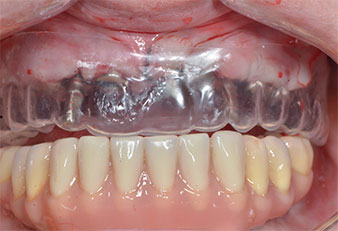

Drei Jahre später war es Zeit für eine gleichartige Oberkieferprothese. Basierend auf der DVT-Planung wurde durch Verwendung kurzer Implantate eine Sinusaugmentation vermieden und die geplanten Implantatpositionen wurden mit einer Bohrschablone auf den Kieferkamm übertragen (Abb. 1 und 2).

Abb. 1: Präoperative Ansicht des Kieferkamms, die Implantatpositionen wurden mithilfe einer Kunststoff-Bohrschablone markiert. Wegen des niedrigen Kieferkamms sind im Seitenzahnbereich sehr kurze Implantate geplant.

Abb. 9: Eine Kunststoffschablone zeigt, dass die Platzverhältnisse ausreichen, um die vorhandene Prothese als Provisorium auf den temporären Implantaten zu verwenden.